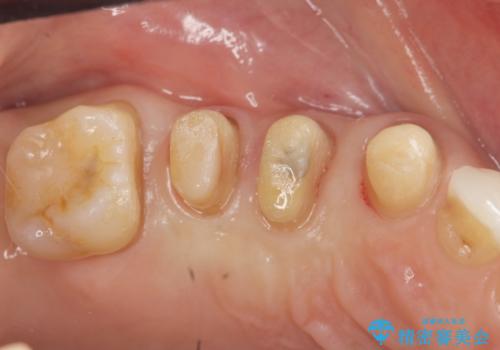

検査の結果、強い歯ぎしりによる歯の周囲の骨の吸収が認められたため歯槽骨の再生・歯周ポケットの除去・力に対抗する連結補綴・補綴前処置としての小矯正を計画します。

今回連結補綴を行うにあたり、歯周病の問題を解決するために再生療法・歯周ポケット除去手術を、またより歯の神経を保存し力に対抗できる環境を整えるために小矯正を行い精度の高いメタルボンドクラウンを製作することができました。